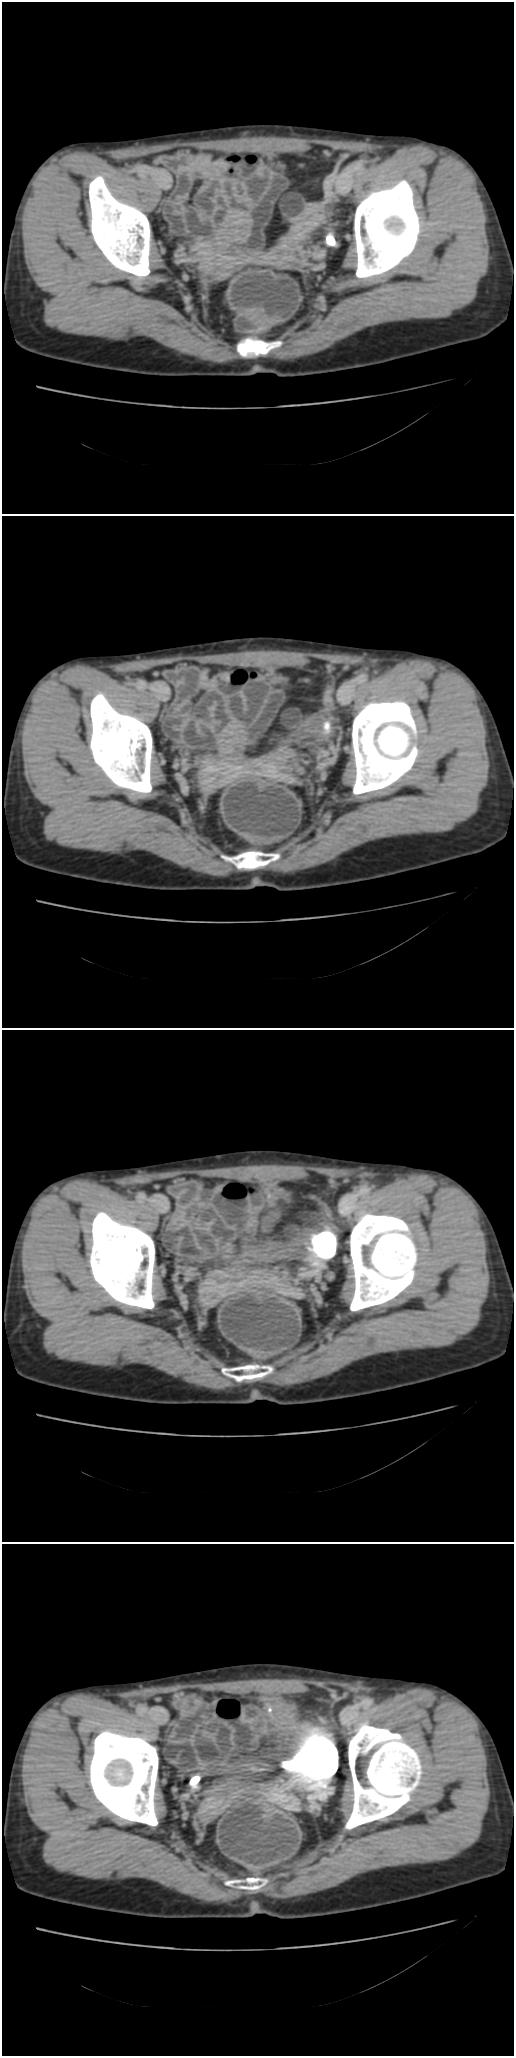

以下是今天的增强片,大家可以看看:

右髂骨见一类圆形略高密度区,似见分层,骨质破坏不明显

考虑良性病变,以动脉瘤样骨囊肿可能性大

右侧髂骨后缘囊状膨胀性骨质改变,无明显骨间隔,周围无明显硬化及骨膜反应,周围软组织无异常,相邻骨组织密度增高,考虑:动脉瘤样骨囊肿可能,要注意与骨巨细胞瘤及转移瘤鉴别。

右侧髂骨膨胀性骨质破坏区 囊内密度尚均匀 骨巨细胞瘤可能性大 动脉瘤样骨囊肿不除外 建议mr观察囊内成分明确诊断 左侧附件区包裹性积液

右侧髂后上棘局限性囊状骨质破坏,大部分界清,似见轻度硬化边,内无分格及钙化,病灶上部局部显示模糊。考虑;骨巨细胞瘤可能大,不除外abc。另可见子宫肌瘤术后子宫缺如。

临床和影像学表现:女性患者46岁,有子宫肌瘤手术病史。影像所见可见残余宫颈部分,左右附件未见新生物;右髂骨翼后端囊状膨胀性骨破坏,囊性部分感觉有强化(楼主标上增强前后的ct值就很好了),未见明确的液—液平面,周边硬化不明显或轻度硬化。

分析:患者年龄46岁,没有明确外伤病史,病变呈膨胀性骨破坏,囊性部分未见明确的液—液平面,周边硬化不明显。综合分析该病例比较符合骨巨细胞瘤,不太符合动脉瘤样骨囊肿。